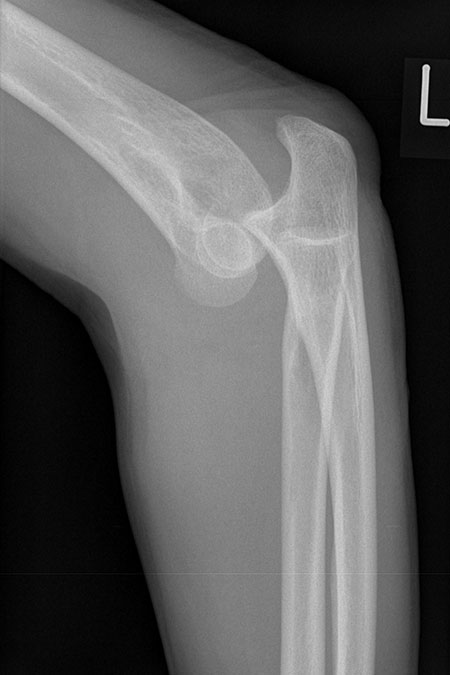

Bei einer Verrenkung (Luxation) des Ellenbogengelenkes kann es zu schweren Verletzungen des Knochens und der Weichteile kommen. Typisch ist der Sturz auf den leicht gebeugten außengedrehten Arm der zu einer Verrenkung (Luxation) des Ellenbogengelenks führt. Dabei springt in den meisten Fällen das Speichenköpfchen über die Oberarmrolle hinweg nach hinten heraus und kann sogar an der Oberarmrolle zerbrechen (Typ Mason IV).

Je nach Ausmaß der Verrenkung reichen die Kapsel- und Bandeinrisse um das Gelenk bis zur Ellenseite herum und führen so zu einer Instabilität des Ellenbogengelenks. Die unkomplizierte Luxation, die schnell einer Einrenkung (Reposition) zugeführt wird, heilt in den meisten Fällen auch ohne Operation aus.

Zeigt die Stabilitätsprüfung des Gelenkes nach Reposition eine Instabilität oder liegen Frakturen vor, wird eine operative Rekonstruktion erforderlich.

Rechtshändiger Fotograf mit hoch instabiler Ellenbogenluxationsverletzung links. Operative Stabilisation mit Rekonstruktion der Bandstrukturen des Ellenbogengelenkes außen und innenseitig unter Einsatz einer Augmentationstechnik (Internal Bracing).

Ventrale Luxation Ellenbogen

Ellenbogengelenk herausgesprungen frontal

Ellenbogengelenk herausgesprungen seitlich